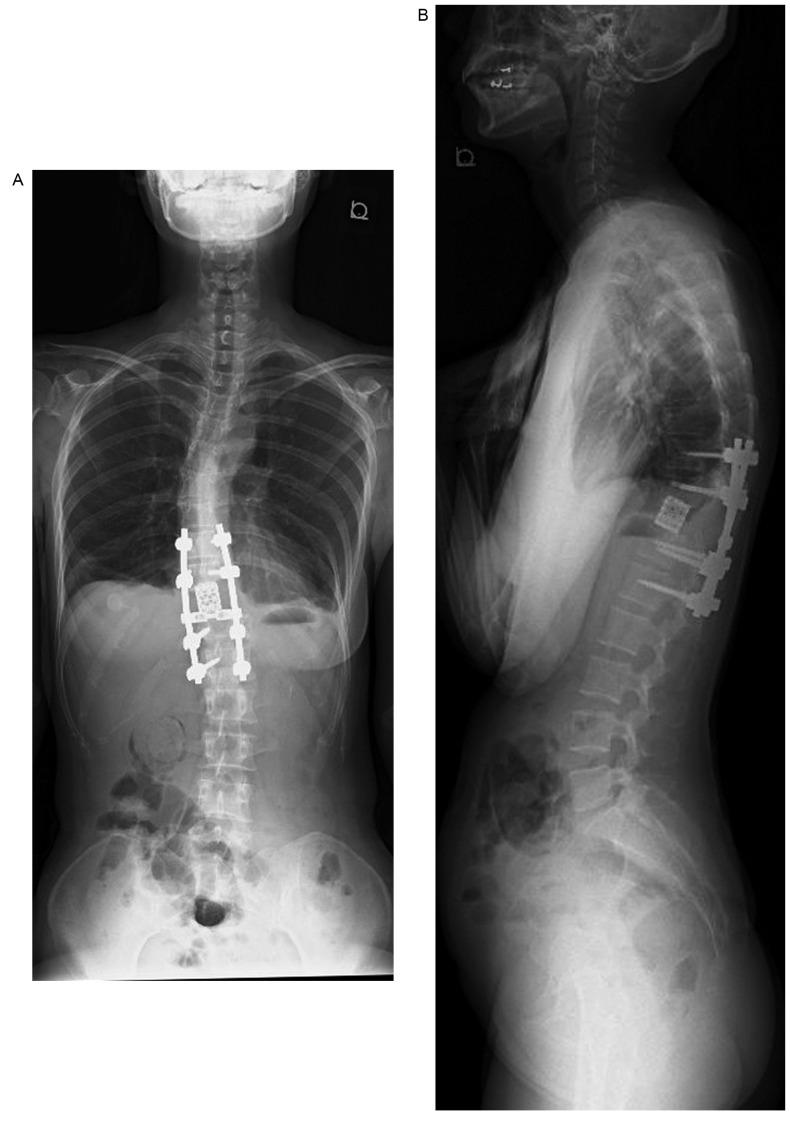

Although denosumab has been reported to induce effective clinical results with respect to tumor shrinkage in a short-term follow-up clinical study, total spondylectomy is recognized as the treatment of choice for eradicating giant cell tumors (GCTs) of the spine. The present study reports the case involving a GCT in the 11th thoracic vertebra complicated by idiopathic scoliosis and treated using total en bloc spondylectomy (TES) with preoperative denosumab therapy. A 35-year-old woman received preoperative denosumab therapy for 8 months, followed by surgery using a computed tomography (CT)-based navigation system that optimized accuracy by recognizing the area of the detached parietal pleura, the irregular border of the collapsed vertebra, and the adjacent vertebra. Complete en bloc resection of the vertebra could be performed, suggesting denosumab can be an effective adjuvant therapy which can reduce the complexity of TES and CT-navigation system facilitated the safe use of this surgical method in a patient with idiopathic scoliosis.

尽管在一项短期随访临床研究中,已报道地诺单抗在肿瘤缩小方面可产生有效的临床效果,但全脊椎切除术被认为是治疗脊柱骨巨细胞瘤(GCT)的首选方法。本研究报告了一例第11胸椎骨巨细胞瘤合并特发性脊柱侧凸的病例,该病例采用术前地诺单抗治疗后行整块全脊椎切除术(TES)。一名35岁女性接受了8个月的术前地诺单抗治疗,随后使用基于计算机断层扫描(CT)的导航系统进行手术,该系统通过识别分离的壁层胸膜区域、塌陷椎体的不规则边界以及相邻椎体来优化准确性。椎体能够被完整整块切除,这表明地诺单抗可以作为一种有效的辅助治疗方法,它能够降低TES的复杂性,并且CT导航系统有助于在患有特发性脊柱侧凸的患者中安全使用这种手术方法。